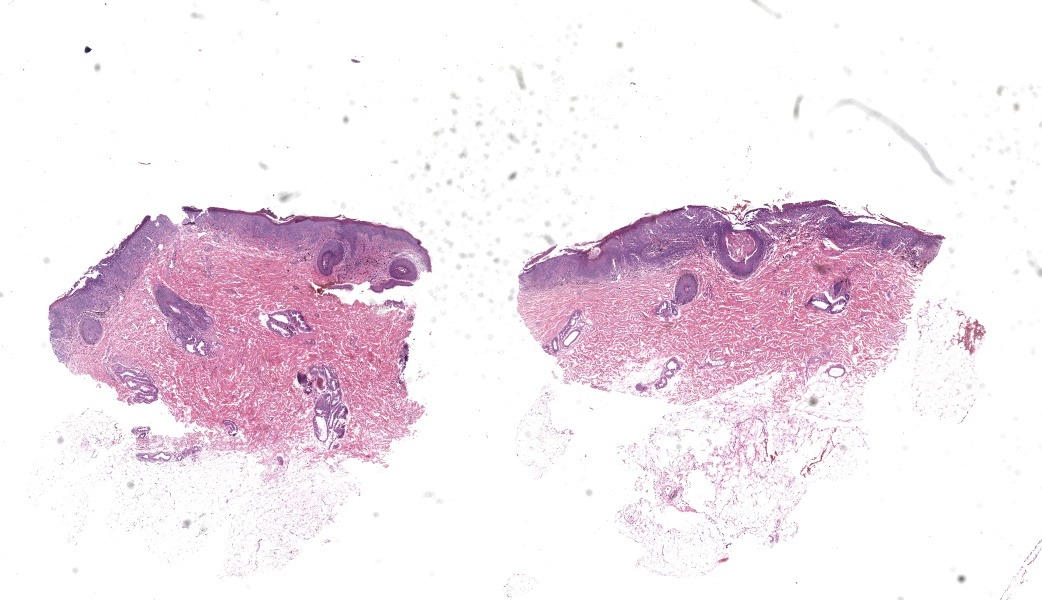

Gross Pathology:Four skin biopsy punches from the abdomen, thigh, neck, and chest were received and processed.

Haired skin. Alle the biopsies are histologically similar. The superficial and mid dermis is obscured by a moderate to severe inflammatory infiltrate, often obscuring the dermo-epidermal junction. The inflammatory infiltrate is represented by a prevalence of lymphocytes and plasma cells, macrophages occasionally engulfing melanin (melanophages), and rare neutrophils. The epidermis is moderately thickened (irregular hyperplasia), with mild intercellular edema (spongiosis) and severe thickening of the stratum corneum by predominantly nucleated (parakeratotic hyperkeratosis) or less frequently non-nucleated keratin (orthokeratotic hyperkeratosis). Numerous apoptotic figures are observed throughout the epidermis, occasionally surrounded by lymphocytic satellitosis. Similar lesions are observed in the hair follicles. There is multifocal erosion or ulceration of the epidermis; the ulcerated areas are obscured by serocellular crusts.Contributor's Morphologic Diagnoses:

MD: Haired skin. Lymphoplasmacytic interface dermatitis, diffuse moderate chronic, with epidermal hyperplasia, numerous suprabasal apoptosis with lymphocytic satellitosis, parakeratosisND: Hyperkeratotic erythema multiforme